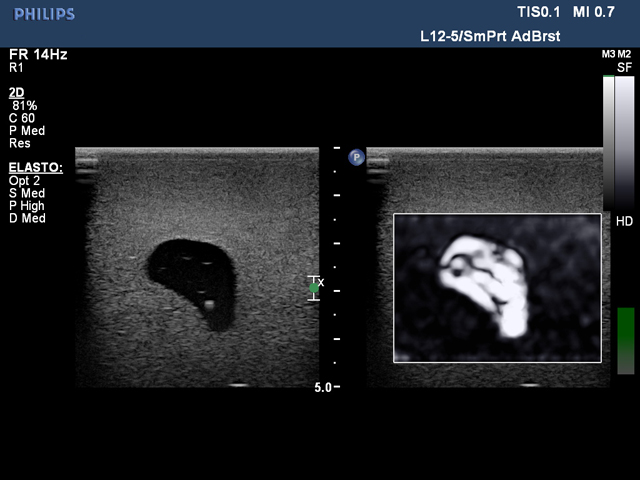

乳房超声弹性成像训练模型给用户提供了一个很好的培训平台,用户可以通过使用本产品练习乳腺弹性成像所需的技能。模型内部的肿块大小不同,便于学生先练习较大病灶的识别和扫描,待熟练后再练习扫描尺寸更小的病灶。